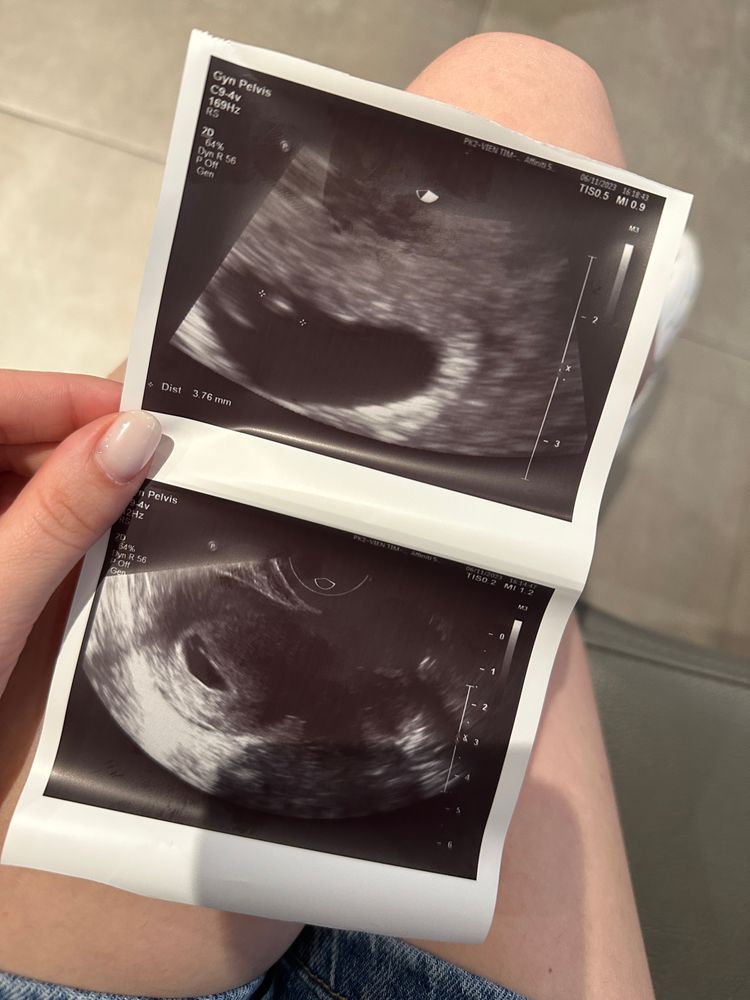

Тина в Благополучная беременность 2 года Первое узи - 6 недель и 2 дня УЗИ, КТГ, доплер Сегодня впервые услышала сердечко своего малыша ♥️ Посмотрите еще 20 записей на эту тему Отменить Ответить ML KH На каком сроке сделали первое узи?) 06.11.2023 Ответить Ирина Легкой вам беременности и родов🌺 06.11.2023 Ответить Не увидели желточный мешок Вес 460 грамм в 22-23 недели Чаты Беременных Выберите чат: Январята-2026 Февралята-2026 Мартята-2026 Апрелята-2026 Майчата-2026 Июнята-2026 Июлята-2026 Августята-2026